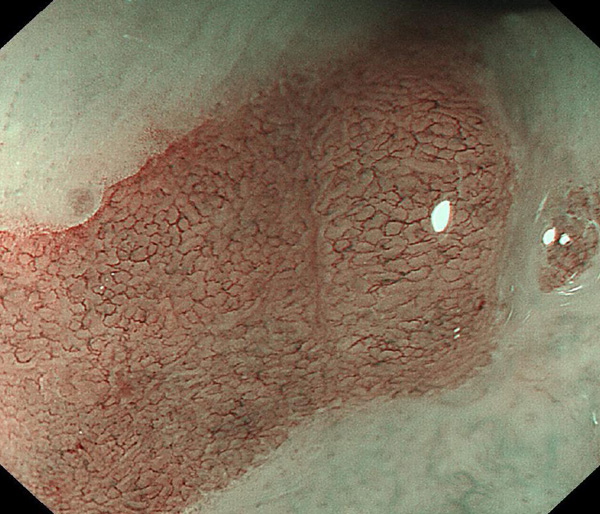

内視鏡所見と病理組織像の1対1対応が可能な症例を公募いたします。主にLSBEに発生した早期癌(HGDを含む)を対象としますが、興味深い症例であればSSBE癌でも結構です。採否は世話人へご一任ください。

特に、本邦では極めて稀なlong segment Barrett’s esophagus(LSBE)から発生した早期癌は、診断に難渋する場合も多く、欧米ではランダム生検による検出が標準的とされています。背景のBarrett食道もろとも全体を内視鏡切除+ラジオ波焼灼する欧米と異なり、ESDで内視鏡的な局所切除が基本の本邦では、存在診断+範囲診断(特に水平)を的確に行うことが不可欠です。

そのためには、一流の病理医による組織学的診断とエキスパート内視鏡医による拡大内視鏡像との一対一対応を徹底的に行うことで、『本来、見えないであろう拡大所見の先にある組織構築像が診えてくる』所まで内視鏡診断レベルを上げていく必要があります。その実現には、一対一対応を追究した症例(特にLSBE発生例)1例でも多く経験するしかありません。本研究会でBarrett食道腺癌(LSBE発生早期病変)を共に学び、拡大内視鏡像の一歩先を診るスキルを習得しましょう!一人でも多くの皆様のご参加をお待ちしています。

私は、Barrett食道癌はHGDも含め、内視鏡による存在診断、範囲診断が可能と信じて来ました。しかし最近、NBI拡大観察を併用しても側方範囲診断が不可能なLSBE症例を経験しました。診断技術を向上させるためには、多くの症例を診るしかありません。そこで、Barrett食道に造詣の深い先生方に世話人をお願いし、Barrett食道研究会を立ち上げることに致しました。全国からLSBE症例を集め、内視鏡的、組織学的診断に迫りたいと思います。皆様のご参加をお待ち致します。